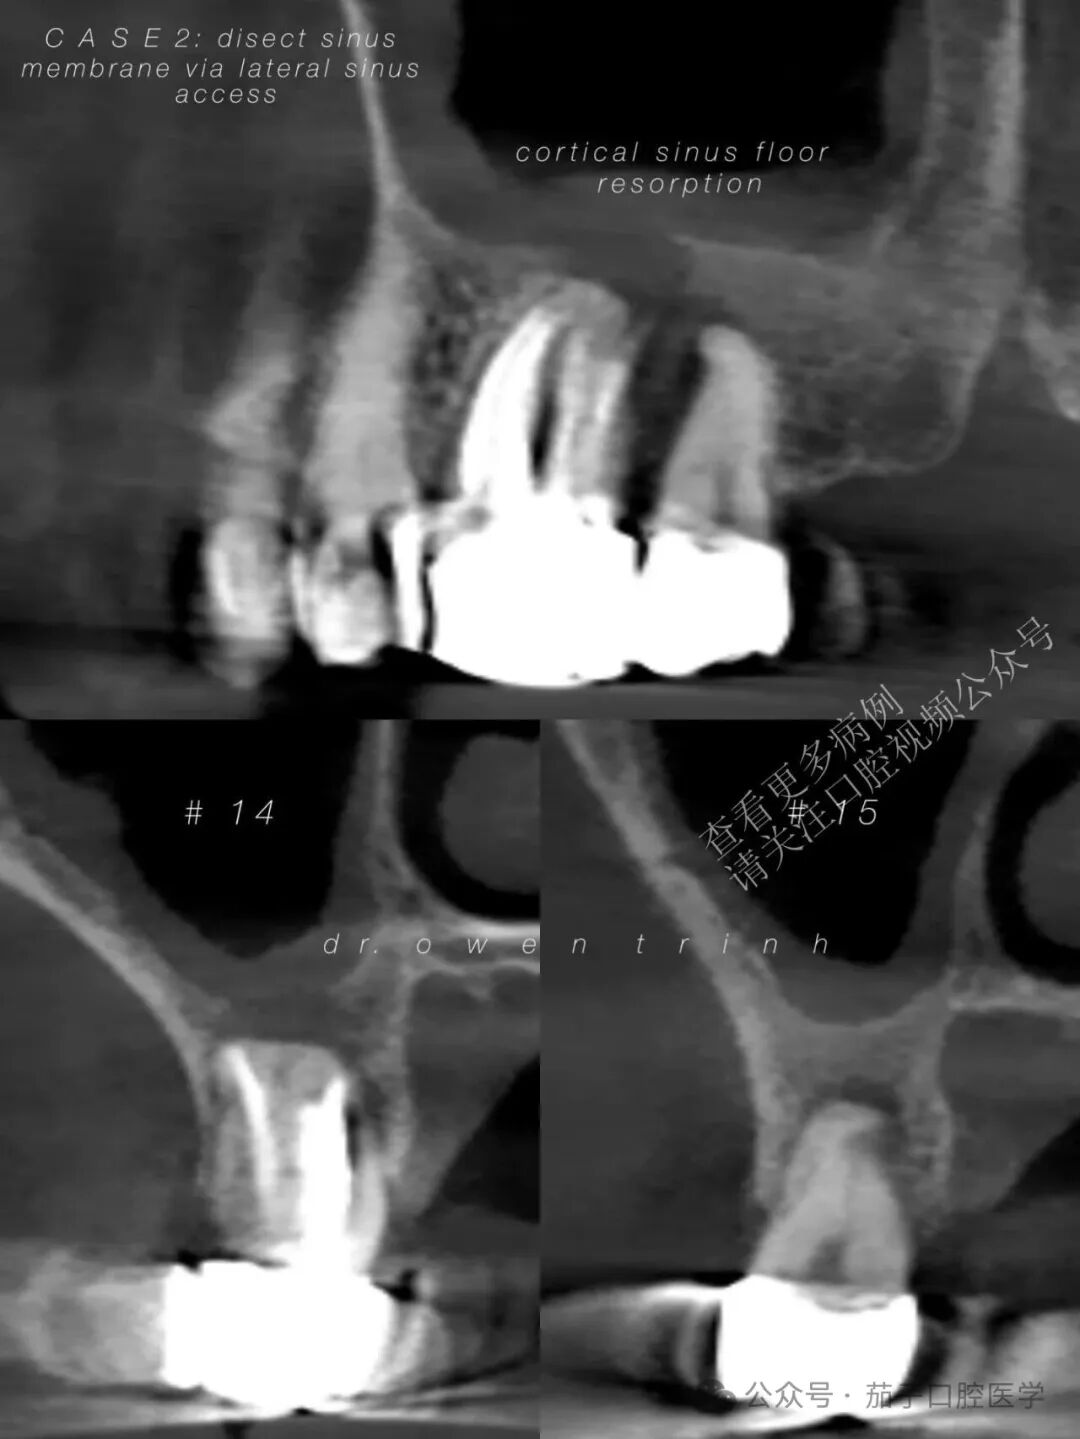

CBCT显示慢性根尖脓肿,已破坏上颌窦皮质底壁及#14与#15牙间的全部邻间壁。患者同意接受拔牙联合外侧上颌窦提升术,为后续种植体植入做准备。

如果不将上颌窦黏膜从脓肿周围的肉芽肿组织上剥离,直接进行拔牙和彻底的根尖刮治,极易导致上颌窦黏膜撕裂。这不仅会造成术中并发症,还可能使后续为种植做准备的上颌窦增量(垂直骨再生)手术变得更加困难。

由于增厚的上颌窦黏膜(慢性上颌窦炎)与脓肿之间存在强烈的粘连/附着,上颌窦黏膜很难与根尖牙槽骨壁分离(在抬升黏膜时阻力极大),这与气化良好的上颌窦底黏膜截然不同。此外,由于缺乏气化的牙槽突骨质,使得抬升上颌窦黏膜变得困难,因为医生必须使用上颌窦刮匙在14号牙和15号牙根尖牙槽骨的每一个转角和曲度中进行操作。